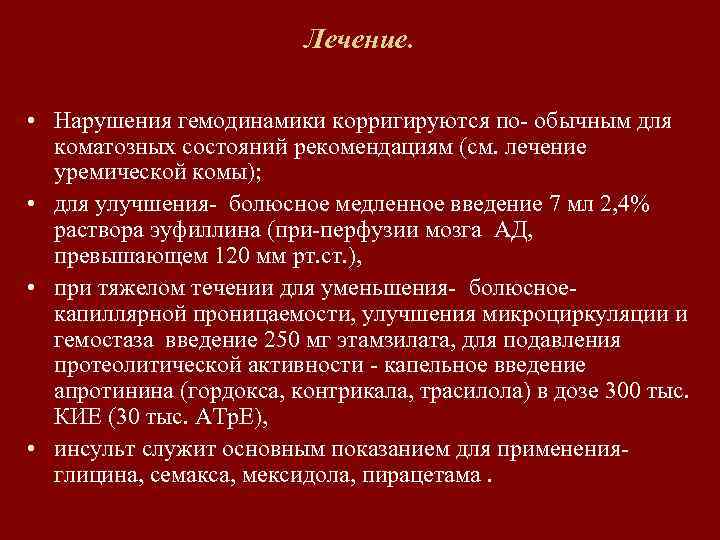

Лечение. • Нарушения гемодинамики корригируются по- обычным для коматозных состояний рекомендациям (см. лечение уремической комы); • для улучшения- болюсное медленное введение 7 мл 2, 4% раствора эуфиллина (при-перфузии мозга АД, превышающем 120 мм рт. ст. ), • при тяжелом течении для уменьшения- болюсноекапиллярной проницаемости, улучшения микроциркуляции и гемостаза введение 250 мг этамзилата, для подавления протеолитической активности - капельное введение апротинина (гордокса, контрикала, трасилола) в дозе 300 тыс. КИЕ (30 тыс. АТр. Е), • инсульт служит основным показанием для примененияглицина, семакса, мексидола, пирацетама.

Лечение. • Нарушения гемодинамики корригируются по- обычным для коматозных состояний рекомендациям (см. лечение уремической комы); • для улучшения- болюсное медленное введение 7 мл 2, 4% раствора эуфиллина (при-перфузии мозга АД, превышающем 120 мм рт. ст. ), • при тяжелом течении для уменьшения- болюсноекапиллярной проницаемости, улучшения микроциркуляции и гемостаза введение 250 мг этамзилата, для подавления протеолитической активности - капельное введение апротинина (гордокса, контрикала, трасилола) в дозе 300 тыс. КИЕ (30 тыс. АТр. Е), • инсульт служит основным показанием для примененияглицина, семакса, мексидола, пирацетама.